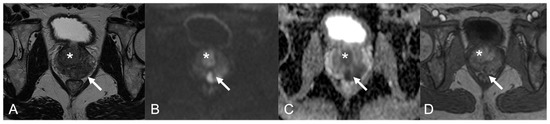

| 6 | PZ diffuse (index lesion PZpm mid-base left; TZa base right | Confluent pseudonodular hypointense areas, capsular bulging; 2-cm marked hypointense irregular TZ lesion | Marked hyperintense; hyperintense | Marked low ADC value; Marked low ADC value | Peripheral rim enhancement and avascular core in the index lesion; inhomogeneous, intense and prolonged enhancement | 5; 5 |

| 8 | PZpm mid-base left | Markedly hypointense nodule, focal capsular bulging | Marked hyperintense | Marked low ADC value | Peripheral rim enhancement, avascular core | 5 |